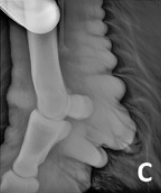

RX Images

In the 2013 Verena K. Affolter (U.C.Davis) study into CPL in Draft Horses there is a brief list of other potential diagnostics including lymphoscintigraphy and lymphangiogram. These procedures are expensive, invasive and unnecessary. Radiographs will show the extent of the folds but again are a surplus cost and show nothing that we can’t already see and feel, with regards to the CPL.